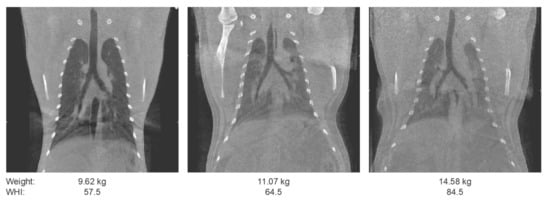

3.1.1. Body Composition

- Sterck, E.H.M.; Zijlmans, D.G.M.; de Vries, H.; van den Berg, L.M.; van Schaik, C.P.; Langermans, J.A.M. Determining overweight and underweight with a new weight-for-height index in captive group-housed macaques. Am. J. Primatol. 2019, 81, e22996. [Google Scholar] [CrossRef]